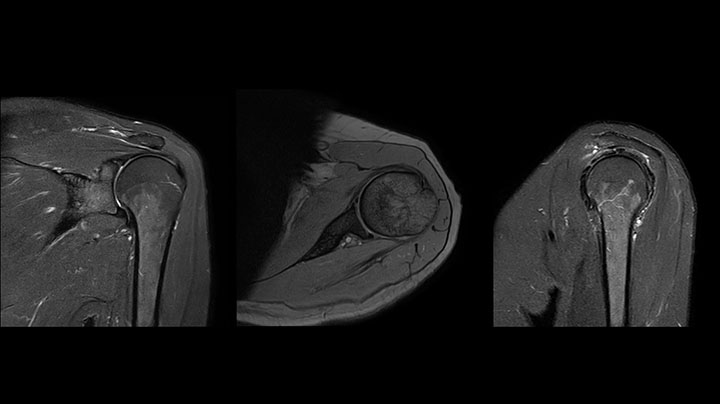

Positioning and operation: smooth and simple Once the scanner was in place, Mrs. Schiffer and her staff received tailored training in line with their clinical and workflow requirements and objectives. “I have been impressed from the start. Installation and set-up were smooth and simple. Within three days, our technologists were confidently using the new system,” recalls Mrs. Schiffer. Since installing Prodiva 1.5T, she and her team have noticed a number of enhancements to their daily work. The scanner’s simple Breeze workflow supports easy patient positioning with fewer positioning steps, rapid set-up and changeover times. Ultra-light anterior coils, short cables and small connectors are making technologists’ lives easier. Senior MRI technologist Sandra Maass says: “Speaking for myself and my colleagues, we all very much enjoy using Prodiva – and we benefit from its many workflow advantages every day.” And Mrs. Schiffer adds, “The flexible, lightweight coils fit really well to the patient’s body shape, and the connectors are superb: connecting and disconnecting requires just little effort.” “The shoulder coil is a great example of easy positioning with Prodiva,” says Mrs. Maass “Other shoulder coils can be quite rigid, so that patients with pain, or bigger stronger shoulders, or a somewhat abnormal shoulder or spine anatomy cannot be positioned well in the coil, which often leads to loss of image quality. However, the Prodiva shoulder coil is very flexible and has large coverage, which makes good positioning easier and that contributes to the superb image quality and high SNR that we get in our shoulder exams.” High quality of images impresses From a clinical perspective, too, Mrs. Schiffer is very impressed with Prodiva 1.5T. In her practice around 50% of scans are neurological, 40% musculoskeletal and the rest made up of vascular, abdominal and miscellaneous cases. The radiology team is receiving good results across anatomies, which their referring physicians are confirming to them. “Prodiva’s high image quality and advanced features, including diffusion-weighted imaging in many organs, improve our diagnostic confidence and help decision-making,” says Mrs. Schiffer. “Prodiva has been an excellent investment and is definitely the right choice for us.” “The quality of the contrast-free MR angiography keeps impressing us,” says Mrs. Schiffer. “In addition to not having to inject contrast agent, these images are amazing, for instance of the carotids. Also our exams of shoulders and hands are really exceptional. Images of the hands, for example, cover the fingertips and include the full wrist as well, all with high signal-to-noise ratio.”

The Prodiva shoulder coil is very flexible and has large coverage, which makes good positioning easier, and that contributes to the superb image quality and high SNR that we get in our shoulder exams.

Scan time 4:19 min, FOV 160 mm, acq voxels 0.55 x 0.80 x 3.0 mm.

Scan time 2:50 min, FOV 160 mm, acq voxels 0.70 x 0.99 x 3.0 mm.